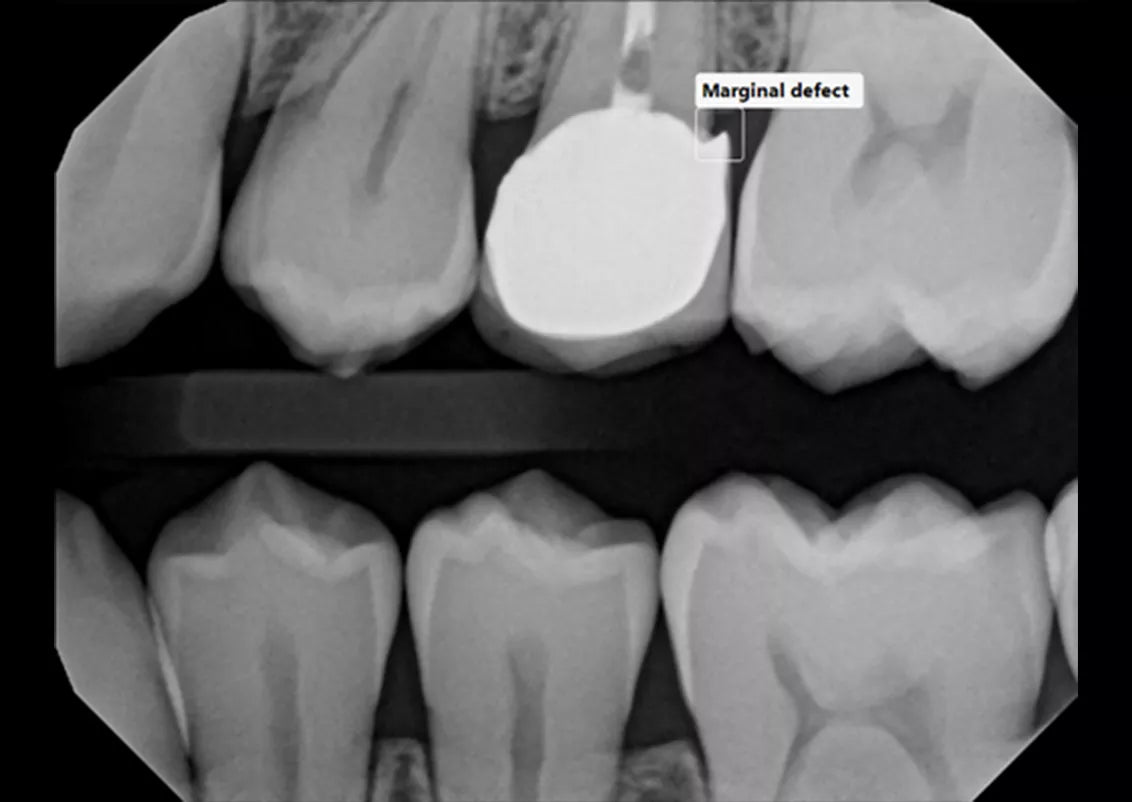

Built into DEXIS™ Imaging Suite Software, the DEXassist Solution provides assisted intelligence with a single click. This new solution enables users to identify up to six dental findings on 2D x-ray images.